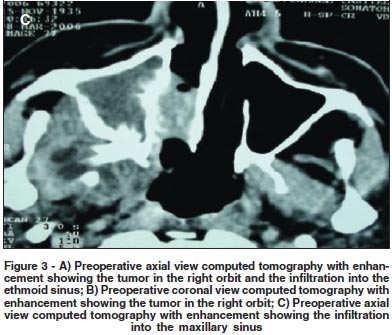

Regarding the malignant neoplasias (seven patients, 58.3%), there were four cases of adenoid cystic carcinoma. The mean age of the patients with adenoid cystic carcinoma was 51 years-old (range, 26 to 65 years-old). Two patients presented a painful palpable mass of rapid growth, proptosis and inferomedial displacement of the globe, and two presented reduced visual acuity, choroidal folds, restricted ocular motility and swelling. Two patients were treated with lateral orbitotomy with resection of the tumor and postoperative radiation, and two were treated with orbital exenteration and postoperative radiation. In these patients, the orbital exenteration and the postoperative radiation were chosen because the preoperative axial and coronal computed tomography showed diffuse orbital involvement, including extraocular muscles and optic nerve. Macroscopically, the tumor was rounded and irregular (Figure 1B). Histologically, two cases were of cribriform pattern (Figure 2C), and two were of solid growth pattern (Figure 2D). One case with cribriform pattern and two cases with solid growth pattern showed necrosis and perineural invasion. The other case with cribriform pattern presented no necrosis and perineural invasion. According to the UICC/TNM Classification, the two cases of cribriform pattern were classified as T2N0M0, and the two cases of solid growth pattern were classified as T4N0M0. The mean follow-up period was 6.5 years (range, 4 to 10 years). No tumoral recurrence was observed in two patients (adenoid cystic carcinoma with cribriform pattern). The patients with solid growth pattern and T4N0M0 developed metastasis to the brain and died of the disease.

The first patient with mucoepidermoid carcinoma was a 70 year-old man, and the second was a 58 year-old woman. Both patients presented a painful palpable mass, proptosis, displacement of the globe off axis, swelling, reduced visual acuity and choroidal folds. The first patient had infiltration into the maxillary and the ethmoid sinus (Figures 3A, B and C) and was treated with orbital exenteration, maxillectomy, ethmoidectomy, postoperative radiation and postoperative chemotherapy. The second patient was treated with lateral orbitotomy with complete resection of the tumor and postoperative radiation. Macroscopically, the second patient showed a soft and reddish tumor (Figure 1C). Histologically, both cases were low-grade and composed of epidermoid cells with mucus-filled vacuoles embedded in a mucoid background (Figure 2E). The mean follow-up was 3.5 years (range, 2 to 5 years). According to the UICC/TNM Classification, the first case was classified as T4N1M0, and the second case was classified as T3aN0M0. The first patient developed metastasis to the brain and died of the disease. The second patient presented no evidence of recurrence of the disease five years after the initial surgery.